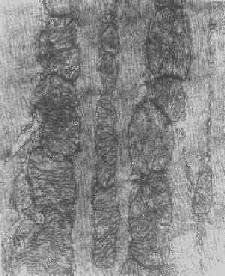

线粒体内晶形包含体(进行性肌营养不良症)

图1-12 线粒体内晶形包含体(进行性肌营养不良症)

根据细胞损伤的种类和性质,可在线粒体基质或嵴内形成病理性包含物。这些包含物有的呈晶形或副晶形(可能由蛋白构成),如在线粒体性肌病或进行性肌营养不良时所见(图1-12);有的呈无定形的电子致

密物,常见于细胞趋于坏死时,乃线粒体成分崩解的产物(脂质和蛋白质),被视为线粒体不可复性损伤的表现。线粒体损伤的另一种常见改变为髓鞘样层状结构的形成,这是线粒体膜损伤的结果。